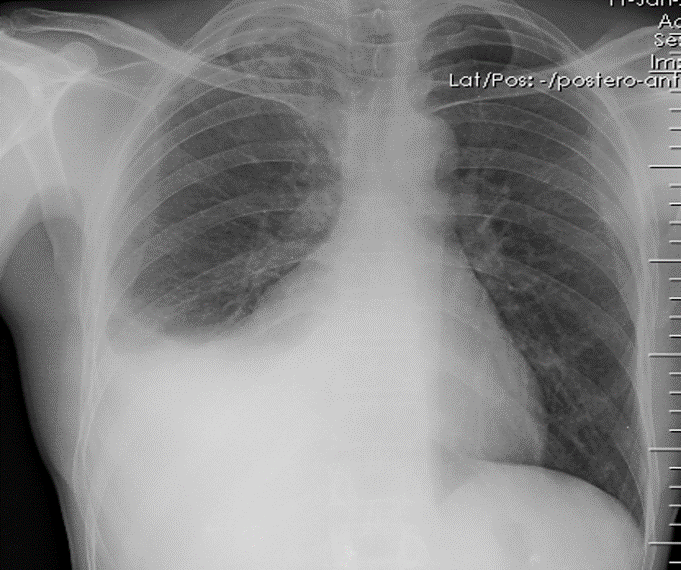

Pleural Effusion

Right sided Pleural Effusion, w/ meniscus sign

Be suspicious of malignancy bc/ large volume